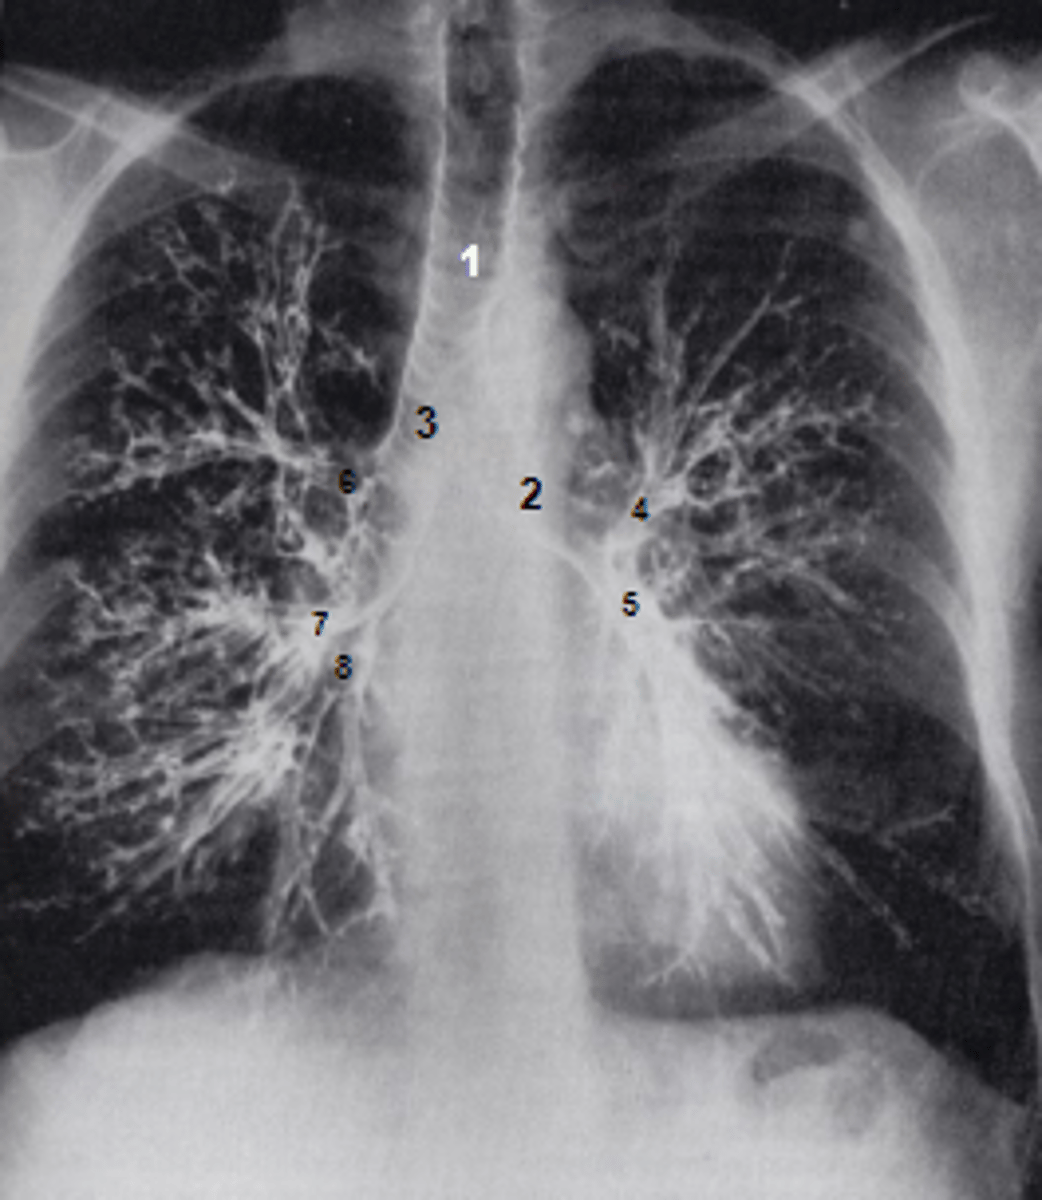

1

at what number is the trachea

2

at what number is the left main bronchus

3

at what number is the right main bronchus

4

at what number is the left superior lobar bronchus

5

at what number is the left inferior lobar bronchus

6

at what number is the right superior lobar bronchus

7

at what number is the right middle lobar bronchus

8

at what number is the right inferior lobar bronchus